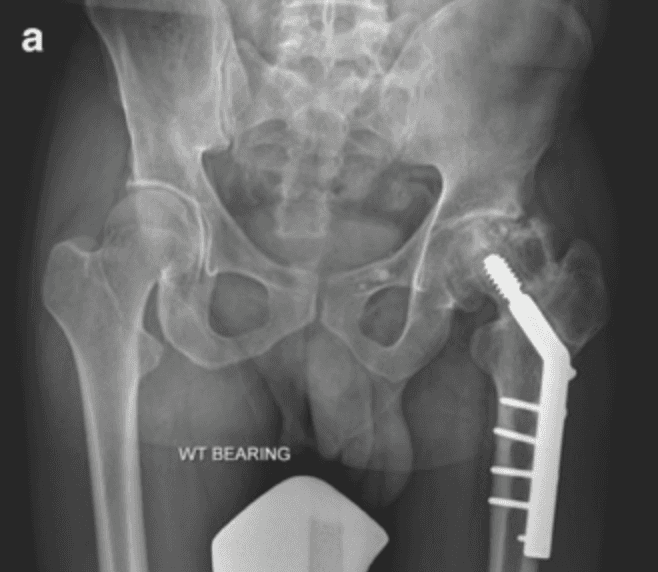

Is simultaneous replacement of both hip possible?

Yes, it is perfectly safe and possible, specifically when hip replacement done using MIS DAA technique as its done in supine position so after finished one side opposite side can done easily with out changing position and does not need preparation again

In DAA technique the patient lies in a supine (on the back) position during surgery allowing both legs to be directly compared and enabling accurate correction of leg length. And that also Ensure better alignment of the new hip. The supine position makes it technically convenient and safe to perform both hip replacements in the same sitting, when indicated.